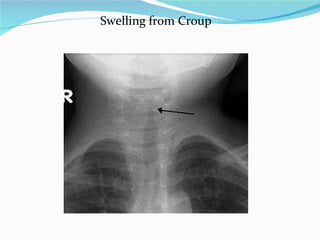

Swelling from Croup

Croup is an infectious illness of the respiratory system involving the voice box and vocal cords. A harsh crowing sound (&quot;stridor&quot;) during inhaling can be heard when the child's air passage becomes abnormally narrowed

It is usually caused by many different viruses, including those responsible for the common cold and influenza.  Occasionally, it is caused by a bacterial infection.  Croup can result in serious breathing difficulties in children. It is more common in babies over 6 months of age and young children, and it occurs more often in boys than girls. It tends to occur more often in the winter months when the weather is colder. Croup